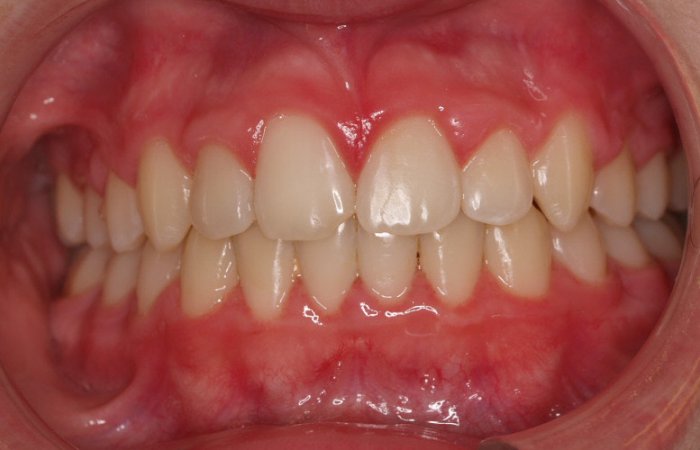

Un “diastema” es una separación extraordinariamente grande entre dos o más dientes. La mayoría de las veces, el diastema aparece entre los dos dientes delanteros superiores. Muchos niños tienen diastema cuando se les caen los dientes de leche, pero en la mayoría de los casos esta distancia desaparece cuando salen los dientes permanentes.

Los diastemas pueden deberse a una diferencia en los tamaños de los dientes, a la falta de algún diente o a que el frenillo labial sea demasiado grande. El frenillo labial es el tejido que va desde el interior del labio hasta la encía, en el lugar donde se sitúan los dos dientes delanteros superiores. Los diastemas también pueden deberse a problemas en la alineación de la boca, como la sobremordida horizontal o la protrusión de los dientes1.

- Realizar un tratamiento ortodóncico para mover los dientes y cerrar el diastema.